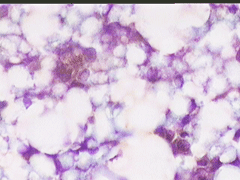

Aσθενής T.E., ετών 47, προσέρχεται το 1998 για α΄φορά στο ιατρείο μας, επειδή κάτι ψηλαφά στον μαστό.

Κατά την κλινικο - υπερηχογραφική διερεύνηση μεταξύ κάτω έξω και κάτω έσω 4μοριου στον δεξιό μαστό. σχετικώς κινητό οζίδιο διαμέτρου 13 χιλ

Yπερηχογραφικώς καλοήθης εικόνα, όπως σε ιναδένωμα

Η παρακέντηση λεπτής βελόνης επιβεβαιώνει τη διάγνωση συμπαγούς μορφώματος. Το ελάχιστο υλικό επιστρώνεται σε αντικειμενοφόρο πλάκα, στεγνώνει στον αέρα με και βάφεται κατά Papanicolaou.

Δείγμα μικροσκοπικών εικόνων: